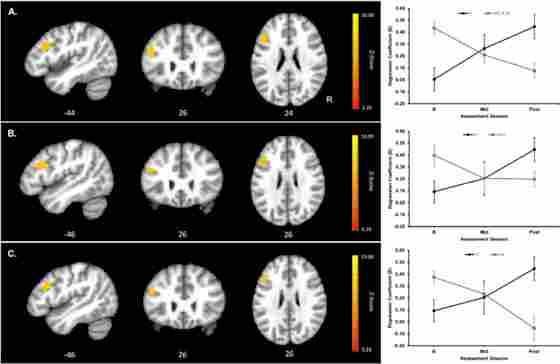

This randomized trial explored changes in processing speed for adult participants to better understand the specific performance improvements that result from cognitive training. The trial utilized 31 healthy older adults (57-71 years), and split them into one of three groups: a cognitive training (CT), physical training (PT), or wait-listed group. Over the span of 12 weeks, the cognitive training group was taught methods of strategic attention, integrative reasoning, and innovation. Results were measured for all participants through an fMRI speed processing task, which measured the speed of participants’ responses as well as the level of activation present in participants’ brains. Though all three training groups showed improvements in reaction time, the CT group’s improvements were the most significant. In addition to reduced response time, brain activation for CT participants decreased, while WLC and AC group activation increased. Faster reaction time coupled with decreased activation in the CT group suggests more efficient brain function.

Cluster showing significant Group × Assessment Session interaction contrast of RT-related parameter estimates and mean RT-related parameter estimates as a function of assessment session and group extracted from the peak voxel within the cluster (peak voxel MNI coordinates shown below the images). Upper panel (A) shows a significant cluster in left prefrontal cortex (PFC) for the CT versus combined WLC and AC group contrasts (k=210 voxels; cluster-wise α=.05 requiring k=82 voxels at a voxel-wise Z=3.28 and α=.001); middle panel (B) shows significant cluster in left PFC for the CT versus WLC group contrast (k=139 voxels; cluster-wise α=.05 requiring k=116 voxels at a voxel-wise Z=3.28 and α=.001); and lower panel (C) shows significant cluster in left PFC for the CT versus AC group contrast (k=126 voxels; cluster cluster-wise α=.05 requiring k=126 voxels at a voxel-wise Z=3.28 and α=.001). Image orientations are in neurological convention indicated with R=Right. Red to yellow indicates increasing strength of the Group × Assessment Session interaction contrast. For assessment session, BL=baseline, Mid=6 weeks into the training or waiting period, and Post=post-training or post-waiting period. Black=Cognitive Training (CT) group, gray=combined Wait Listed Control (WLC) and Active Control (AC) group in A, gray=WLC group in B, and gray=AC group in C. Errors bars show SEM.